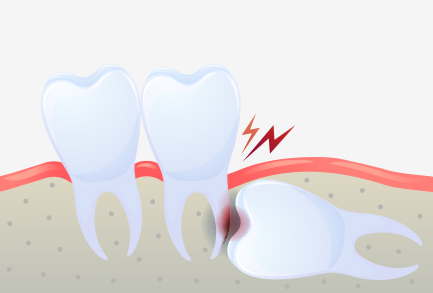

비정상적인 위치에 매복되어 자란 사랑니는

염증과 통증을 일으킬 수도 있으므로

발치하는 것이 좋습니다.

누워서 자란 사랑니의 경우

바로 앞의 어금니 뿌리를 압박해 염증을 일으키거나

턱뼈의 신경까지 손상시킬 수 있습니다.

사랑니와 어금니 사이에 음식물이 끼게 되어 충치 및 치주염 발생의 위험율이 높아집니다.